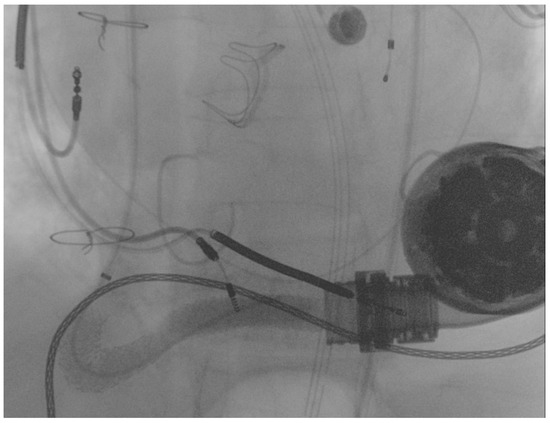

Following this first LVAD intervention, a dual antithrombotic regimen with aspirin and a vitamin K antagonist (VKA) was administered. However, antiplatelet therapy was suspended few months after due to a major neurological bleeding. At admission, the patient showed unstable clinical conditions (systemic blood pressure of 90/60 mmHg, a heart rate of 130 beats per minute, a respiratory rate of 20 breaths per minute, arterial oxygen saturation of 85%). Laboratory markers showed elevated serum lactate and impaired renal function, without signs of ongoing hemolysis. Due to the impeding cardiogenic shock, the patient was admitted to intensive care unit (ICU). Echocardiographic evaluation confirmed the presence of severe LV dysfunction (ejection fraction < 25%) and dilation. Moreover, severe right ventricular (RV) dysfunction (TAPSE < 15 mm) was found. LVAD logged several low-flow alarms (1.5 L/min, 8000 rpm), suggesting that a major device failure could be the trigger of this condition. Considering the unstable clinical setting and the past medical history of OGO [8], computed tomography (CT) was deferred and the patient was directly transferred to the catheterization laboratory to perform an urgent invasive diagnostic assessment. The procedure was performed under general anesthesia and with continuous transesophageal echocardiography monitoring. In order to avoid possible circulatory collapse during the procedure, both the arterial and venous femoral accesses were surgically obtained with the purpose of rapidly deploying veno-arterial extracorporeal membrane oxygenation (ECMO) assistance, if necessary. Via the right femoral artery, a first attempt at performing angiography using a diagnostic pig-tail catheter failed. Considered the presence of a known kinking site [8], an 8F 110 cm-long sheet (Flexor®Ansel Guiding Sheath, Cook Medical, Bloomington, IN, USA) was conducted through the distal anastomosis of the outflow graft to provide further support. Following this, a 130 cm-long supporting catheter (TrailBlazer™, Medtronic) over standard 0.035″ × 260 cm hydrophilic guidewire was advanced beyond the kinking and a diagnostic angiography was performed. As showed in Figure 2, a discrete filling defect located at the kinking site was found, suggesting recurrent thrombosis.

Figure 2.

Diagnostic angiography showing recurrent outflow graft obstruction (yellow arrow).